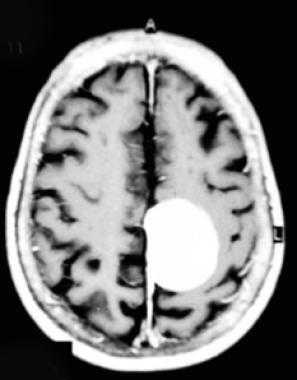

МРТ-признаки метастазов в мозг

МРТ — более чувствительный и специфичный метод в выявлении метастазов ЦНС по сравнению с компьютерной томографией. Вторичные опухоли имеют ряд общих черт при МР-исследовании.

Т1 ВИ (без контрастного усиления)

- Изоинтенсивный либо умеренно гипоинтенсивный сигнал по отношению к белому веществу мозга от активной части опухоли

- Гипоинтенсивный сигнал от центральной зоны (некроза и распада)

Т2 ВИ

- Гиперинтенсивный сигнал от центрального участка метастаза

- Повышение интенсивности сигнала от отечных тканей мозга, окружающих вторичную опухоль, вследствие чего метастазы становятся более четкими на изображениях

МРТ с контрастным усилением

- Выраженное увеличение интенсивности сигнала

- Усиление сигнала по периферии в виде «кольца» или «короны»

- Помогает дифференцировать кровоизлияиния в метастаз от геморрагического инсульта (выраженное усиление сигнала на Т1 ВИ)

Метастазы головного мозга на МРТ. Фото. Определяются множественные метастазы в мозг при раке легкого: слева в режиме Т1-ВИ в виде гипоинтенсивных образований, справа — в режиме Т2-ВИ виде множественных участков повышенного сигнала, окруженных зоной перифокального отека. У пациента подтверждена первичная опухоль легкого.